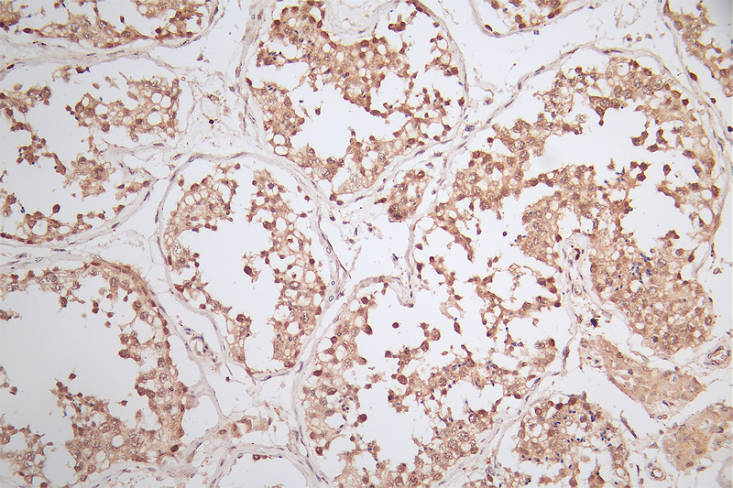

IHC image of CSB-RA620753A0HU diluted at 1:50 and staining in paraffin-embedded human testis tissue performed on a Leica BondTM system. After dewaxing and hydration, antigen retrieval was mediated by high pressure in a citrate buffer (pH 6.0). Section was blocked with 10% normal goat serum 30min at RT. Then primary antibody (1% BSA) was incubated at 4°C overnight. The primary is detected by a Goat anti-rabbit polymer IgG labeled by HRP and visualized using 0.79% DAB.